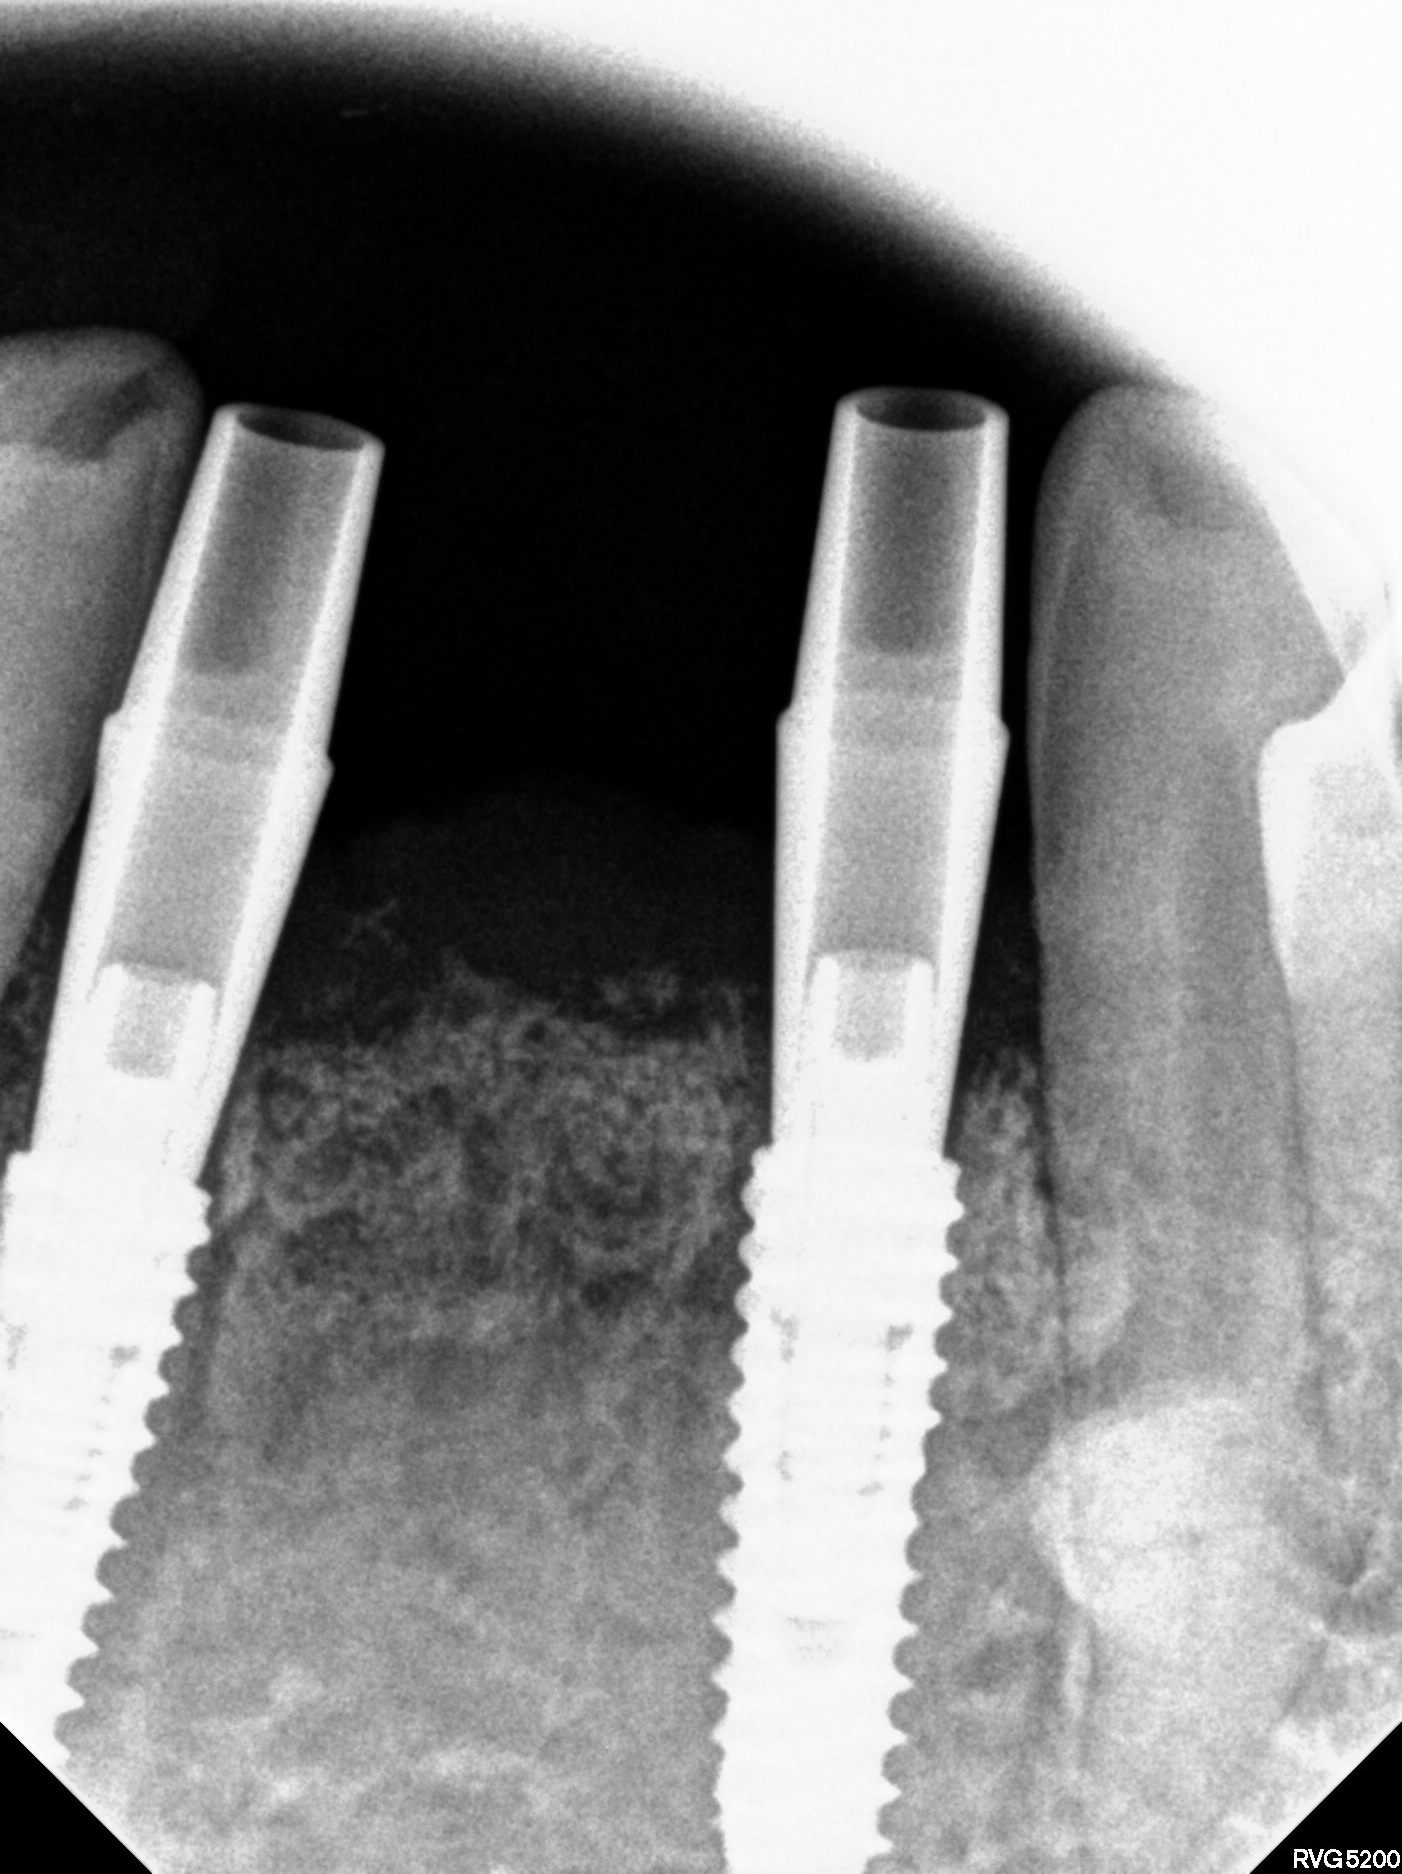

CT와 구강스캔 데이터를 결합해, 신경·혈관·골의 두께까지 고려한 3D 시뮬레이션을 통해 최적의 식립 위치를 결정합니다.

CT와 구강스캔 데이터를 결합해 수술 전 3D 시뮬레이션으로 식립 위치·각도·깊이를 정밀 계획합니다.

임플란트 식립위치 결정

임플란트 식립